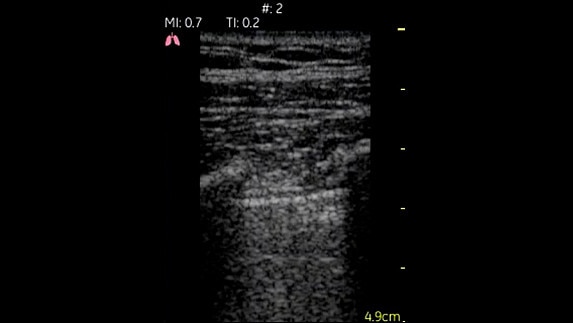

Lungs